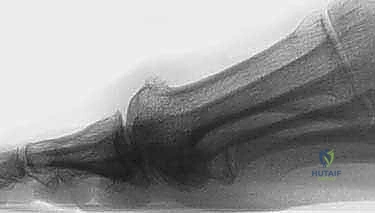

2. عملية موبيرج لقطع العظم (Moberg Osteotomy): إعادة توجيه الحركة

على الرغم من أن الشايليكتومي تزيل العائق، إلا أن المفصل قد يظل مقيداً بسبب تقلص الأنسجة الرخوة أو التغيرات الهيكلية طويلة الأمد. هنا تأتي عبقرية عملية موبيرج، والتي سُميت على اسم الجراح السويدي إريك موبيرج.

هي عبارة عن عملية "قطع عظم إسفيني إغلاقي ظهري" (Dorsal closing-wedge osteotomy) في قاعدة السلامية القريبة (عظمة الإبهام الأولى). بعبارة أبسط، يقوم الدكتور هطيف بإزالة مثلث صغير جداً من العظم من الجزء العلوي للإصبع، ثم يغلق هذه الفجوة ويثبتها.

السر الميكانيكي الحيوي لعملية موبيرج:

هذه العملية لا تزيد من النطاق الكلي لحركة المفصل، بل تعيد توجيه هذا النطاق. إنها تقوم بـ "اقتناص" بضع درجات من الانثناء الأخمصي (الثني لأسفل - والذي غالباً ما يكون لدى المريض فائض منه ولا يحتاجه كثيراً في المشي العادي) و"منحها" للانثناء الظهري (الثني لأعلى - وهو ما يحتاجه المريض بشدة لدفع القدم أثناء المشي). هذا التعديل الزاوي البسيط يرفع الإبهام بعيداً عن منطقة الاحتكاك المؤلمة، مما يحسن الوظيفة بشكل دراماتيكي.

الآن، ينتقل التركيز إلى السلامية القريبة (عظمة الإصبع). على بعد حوالي 5 مليمترات من سطح المفصل، يقوم الدكتور هطيف بعمل قطعين عظميين لإنشاء شكل "إسفين" (مثلث) قاعدته متجهة لأعلى (ناحية ظهر القدم). يتم إزالة هذا الإسفين العظمي الصغير جداً (عادة بعرض 2-3 ملم).